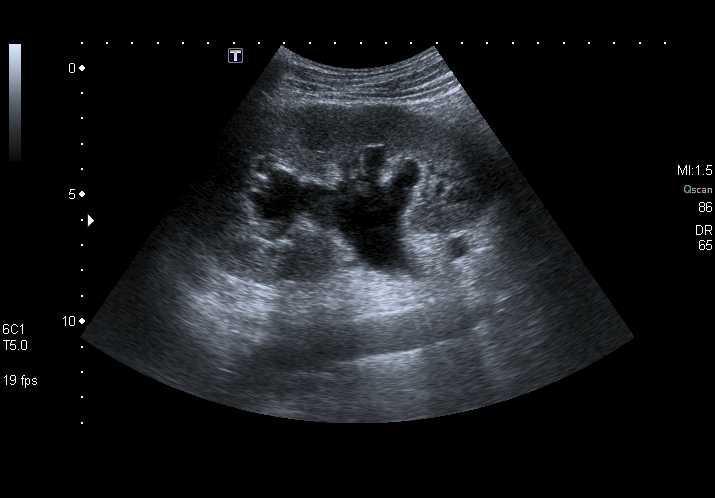

![]()

Hydronéphrose modérée. © POCUS Atlas